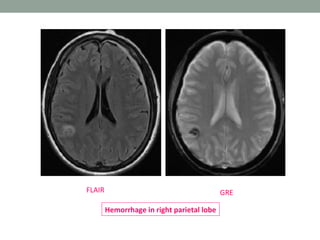

Gradient echo (GRE)

• In a GRE sequence, a RF pulse is applied that partly flips

the NMV into the transverse plane (variable flip angle).

• Gradients, as opposed to RF pulses, are used to dephase

(negative gradient) and rephase (positive gradients)

transverse magnetization.

• These gradients do not refocus field inhomogeneities.

• This feature of GRE sequences is exploited- in detection

of hemorrhage, as the iron in Hb becomes magnetized

locally (produces its own local magnetic field) and thus

dephases the spinning nuclei.

• The main clinical application of GRE sequence is

detection of hemorrhage, micro bleeds, iron deposition

and calcification.

GREFLAIR

Hemorrhage in right parietal lobe